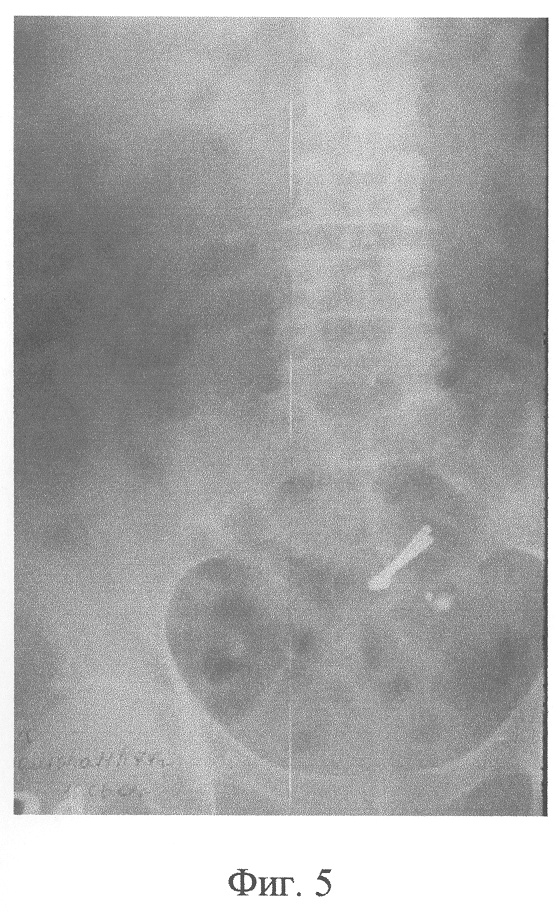

Фиг.5 – рентгенограмма больной Б., первые сутки после операции, сформирован Т-образный толстокишечный анастомоз с применением компрессионных устройств;

В ходе операции после выполнения лапаротомии произвели мобилизацию и резекцию сигмовидной кишки. При этом проксимальный отрезок нисходящей ободочной кишки был выведен на переднюю брюшную стенку с формированием плоской колостомы. Оба отрезка обработали и произвели их рассечение до слизистой, на обработанные участки установили компрессионные устройства, выполненные из никелида титана марки ТН-10. Вслед за этим отрезки Т-образно сопоставили и соединили между собой однорядным узловым экстрамукозным швом. Операцию завершили ушиванием наглухо брюшной полости (Фиг.5).